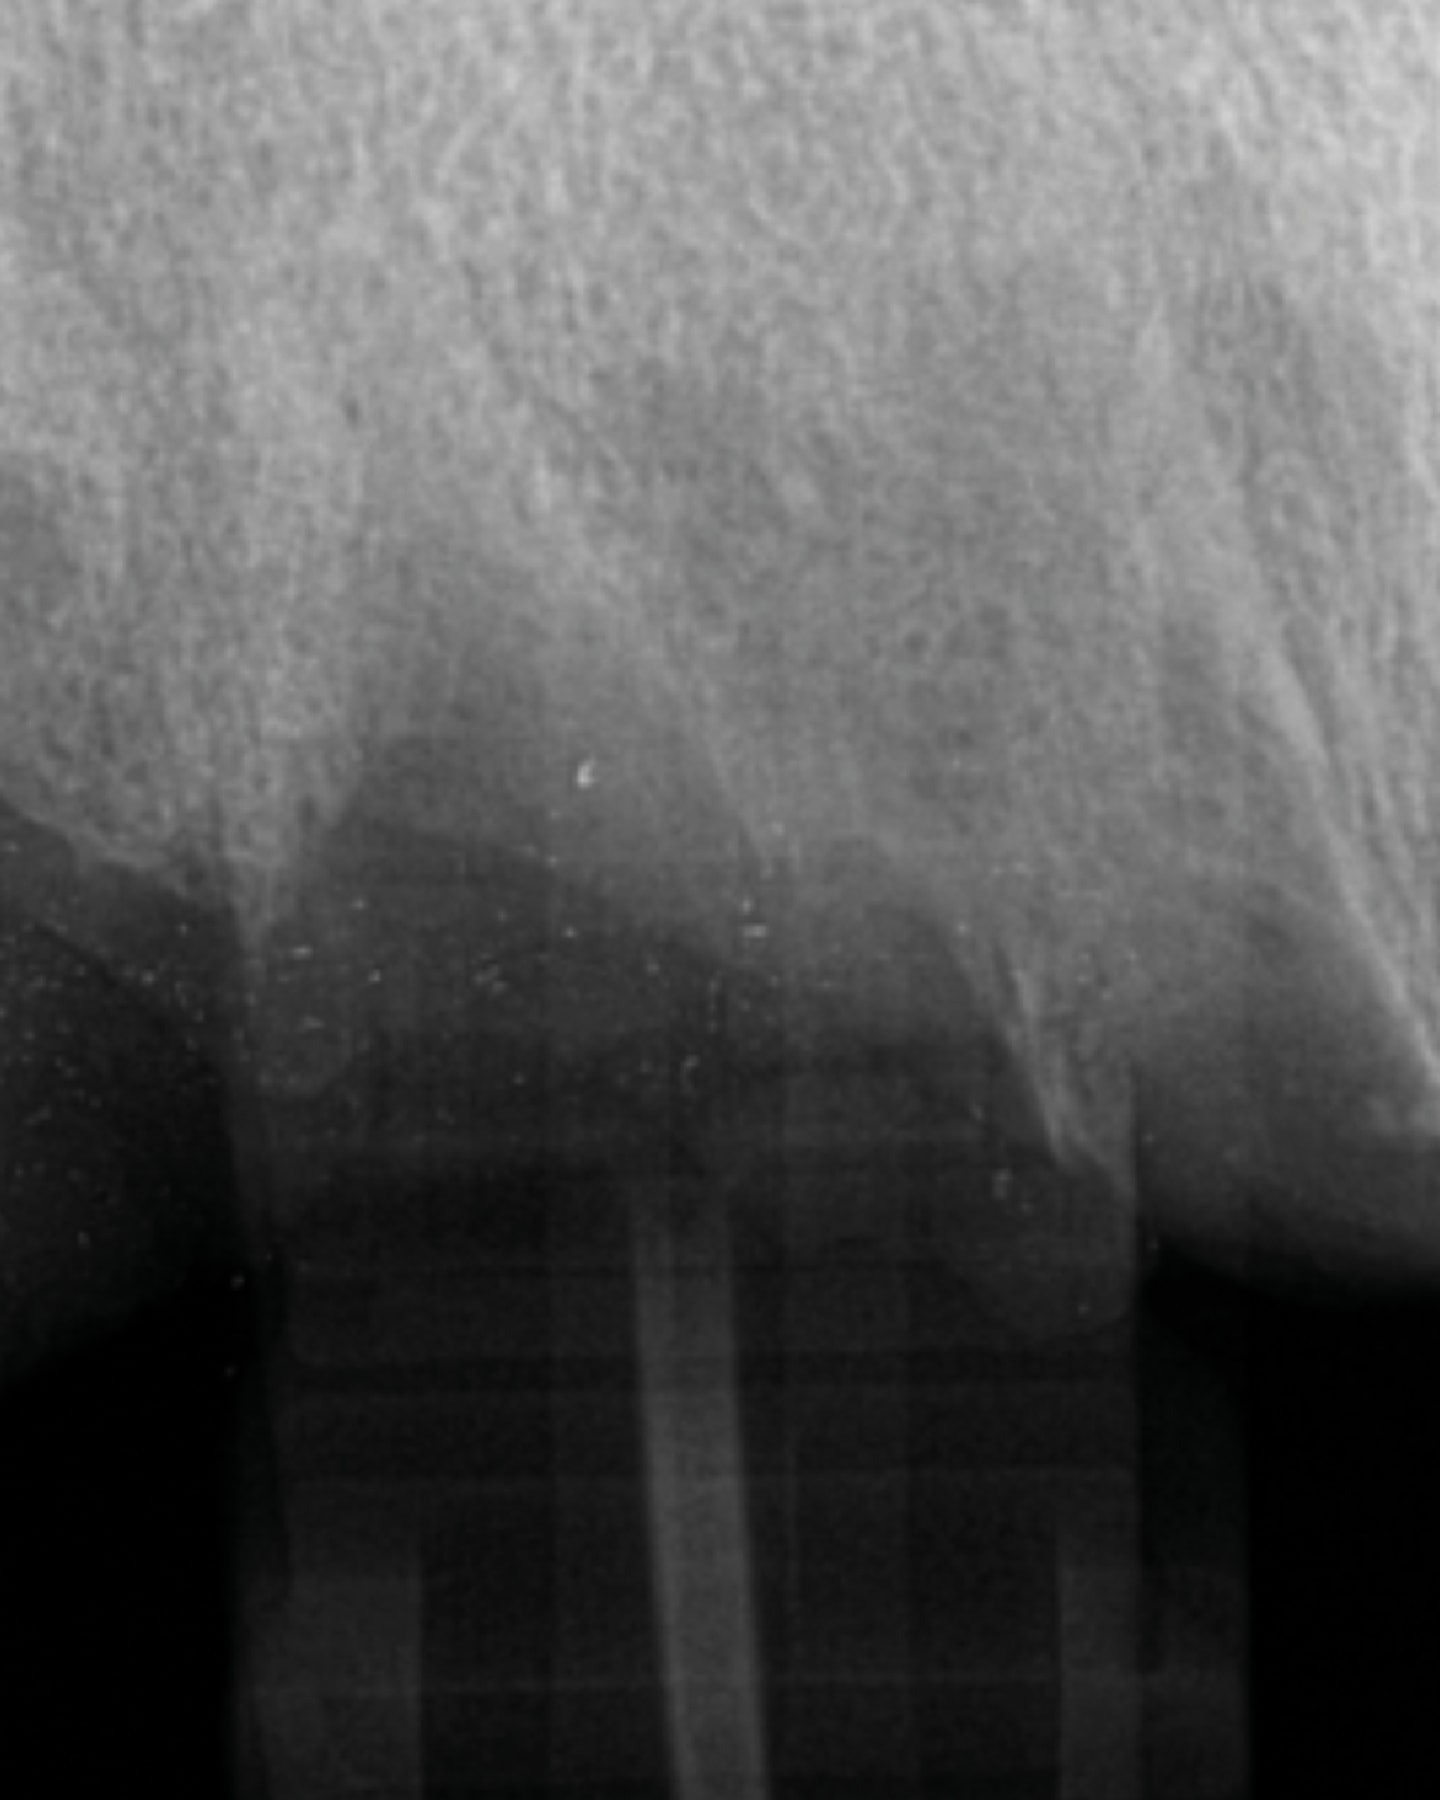

Radiographically, teeth presenting with mobility will have a widened PDL space and less dense bone surrounding that tooth (Figure 1). Utilization by the patient of LMHFV for 5 minutes daily stimulates the bone, increasing the density with a decrease in the PDL space and associated improvement in the mobility returning to a healthy periodontal state (Figure 2).